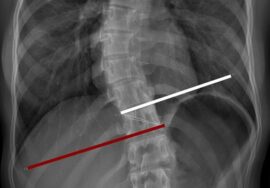

جراحة اعوجاج العمود الفقري (الجنف) تهدف إلى تصحيح الانحناء الغير طبيعي في العمود الفقري، وذلك باستخدام قضبان معدنية ومسامير لتثبيت الفقرات في وضعية أكثر استقامة. يُوصى بها عادةً في الحالات الشديدة، أو عندما يستمر الانحناء في التزايد رغم استخدام الجبائر أو التمارين العلاجية.